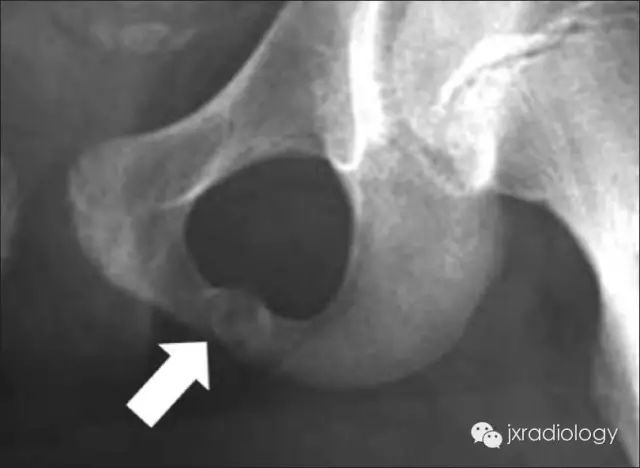

X线:骨盆正位片为常规检査。在患侧坐骨耻骨结合处可见到骨皮质膨隆,有时出现层状改变,膨隆部位密度浓淡不均,中央可见类圆形透光区,偶有骨皮质破裂影像,膨隆周围可见硬化改变。

CT:CT具有高密度分辨力和横断面成像特点并可三维重建,可见坐骨耻骨结合处局限性膨大,有破碎,其内有低密度透光区,边缘不规则,骨质断裂不连接,骨髓腔有硬化变现。无明显的死骨和骨膜反应,邻近的软组织正常。

本病由于发病部位较特殊,转归较好,可自愈且无任何后遗改变,如认识不足极易漏诊和误诊。临床上有髋关节或大腿根部疼痛,有剧烈运动史的患儿,在就诊时应考虑本病存在的可能。影像学检查发现坐骨耻骨结合处骨质隆起,密度不均匀,有低密度透光区典型表现,MRI上周围组织有水肿表现,不论有无临床表现均可诊断本病。